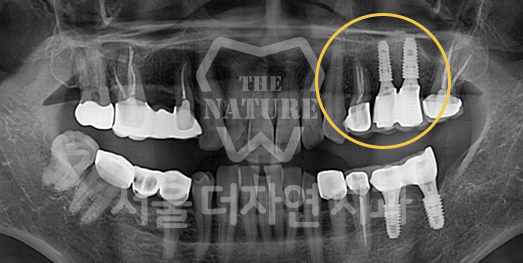

전체 임플란트

위 아래 치아가 정확하게 맞아야하는 고난이도 임플란트

임상 경험이 많은 숙련된 전문의의 섬세한 기술력이 중요합니다.

치료기간 : 2021.04.12~2021.09.15